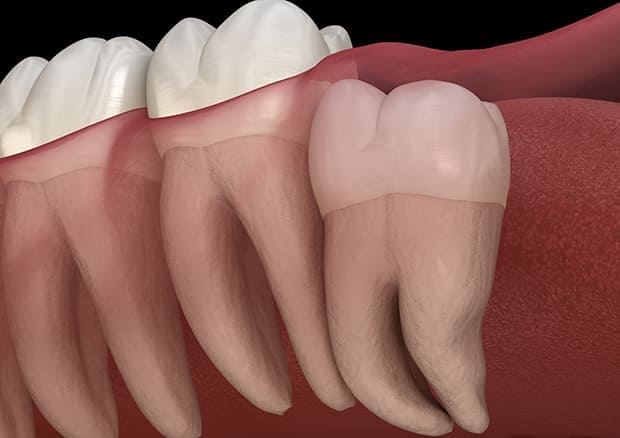

水平埋伏の親知らず

歯茎の中で完全に横に生えてしまうタイプです。

この親知らずを水平埋伏智歯と言います。このタイプはほとんどが下顎のケースです。真横に生えているので抜歯の際は難易度が高く2~3つに砕いて分けて抜歯をします。